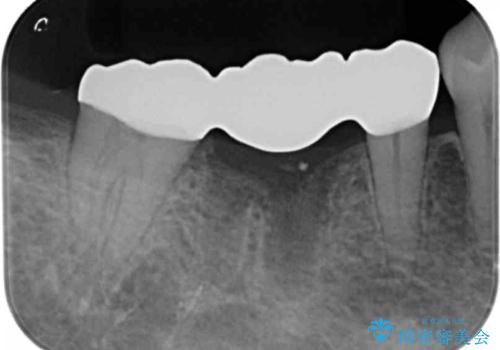

また、根の詰め物が根尖孔外(根の先の外の骨の部分)に盛大に漏れ出しており、歯周ポケットと根尖病巣が交通しているような状態でした。

歯がなくなったところに関しては、ブリッジで修復することにしました。